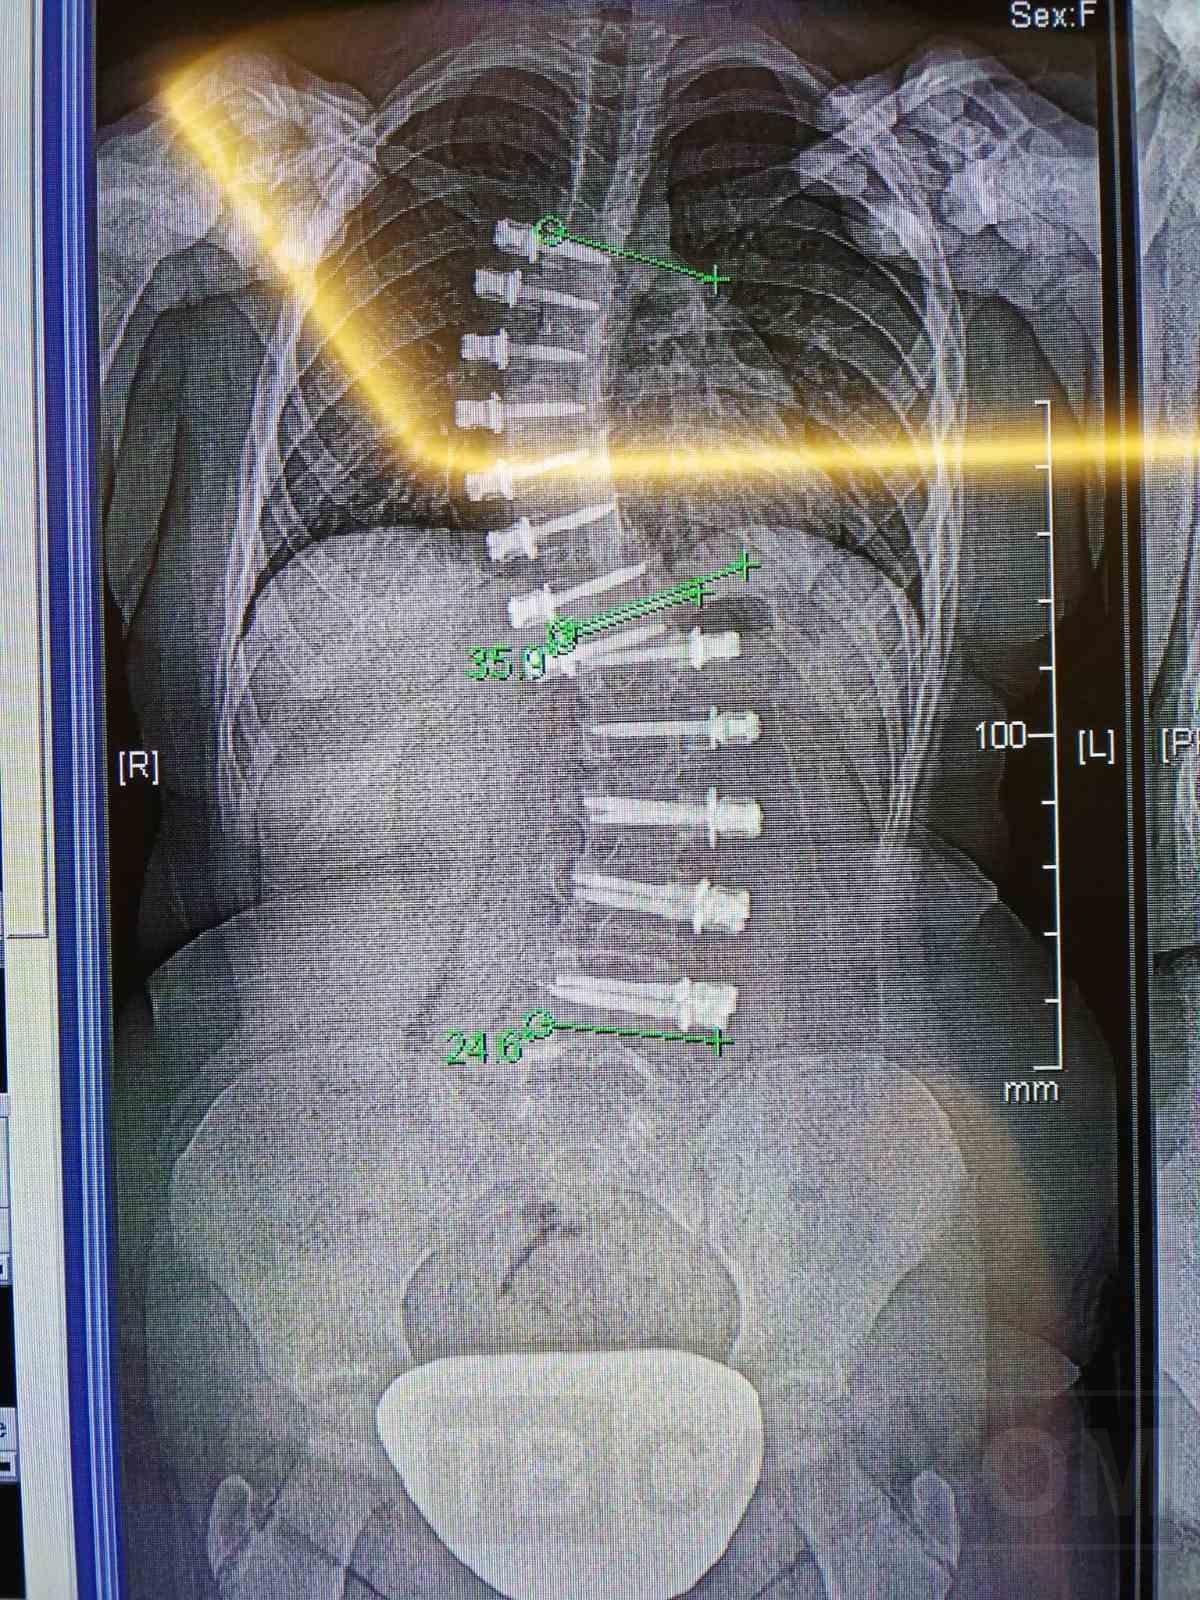

Бояна е едва на 14 години. От съвсем малка води тежка битка със сколиозата. Животът ѝ преминава в кинезитерапевтични салони и басейни, а от 4-годишна носи корсет. Преди няколко години претърпява първата си операция в клиника в Турция по иновативен метод, но след инцидент се налага битката да започне отново. За всичко това и за предстоящото лечение на детето ни разказа нейната майка.